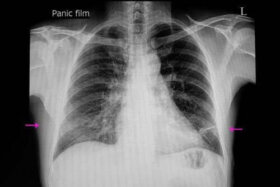

폐확장부전이라는 말은 atele-vs(불완전)라는 단어와 éktasis(확장)이라는 단어에서 비롯되었다. 이는 폐 내부의 공기량이 매우 결핍된 폐의 이상 상태다. 이 글에서는 폐확장부전의 증상과 원인에 대해 살펴볼 것이다. 이 문제는 폐 전체 또는 일부에 영향을 미칠 수 있다. 일반적으로 이는 기도가 막히거나 폐의 외부에…